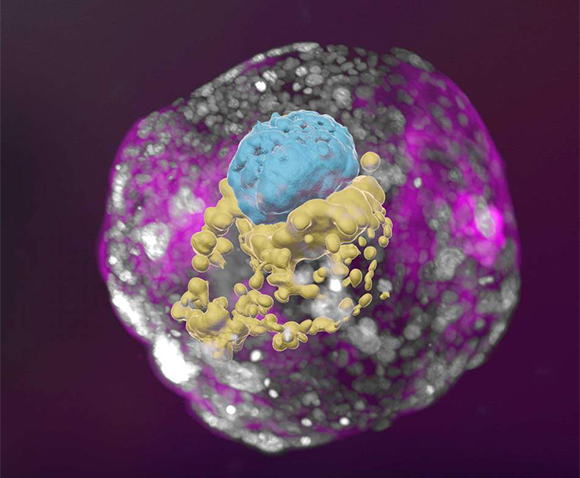

חוקרים במכון ויצמן למדע הצליחו לגדל במעבדה עובר מלאכותי של אדם למשך 14 יום, משך זמן חשוב לתחילת התפתחות האיברים. החוקרים השתמשו בתאי גזע וברחם מלאכותי, כדי לגרום לתאים להתחלק ולהתמיין כפי שקורה בעובר המתפתח ברחם לאחר ההפריה. העובר המלאכותי פיתח את הרקמות המופיעות בעובר טבעי בגיל הזה, בהן שכבות התאים המתפתחות לשק השפיר והשליה. מודל כזה מאפשר לעקוף אילוצים אתיים הכרוכים בחקר עוברים של אדם, ולחקור לעומק את שלבי ההתפתחות הראשוניים, ואת התהליכים המובילים להתפתחות שכבות התאים הראשונות ומהן הרקמות והאיברים. “החודש הראשון להיריון הוא עדיין במידה רבה קופסה שחורה, הן בשל מגבלות אתיות על המחקר בעוברי אדם והן בשל קשיים טכניים”, אמר ראש צוות המחקר, יעקוב חנא. “המודל המלאכותי שלנו מציע דרך אתית ונגישה להציץ לתוך קופסה זו; הוא מחקה באופן אמין את התפתחות העובר הטבעי ואת היווצרות המבנה המורכב והמופלא שלו”. למחקר.

מודל עוברי (עובר מלאכותי) בשלב המקביל ל-14 ימי התפתחות בעובר אמיתי. שק חלמון (צהוב), החלק שיהפוך לעובר עצמו ולשק השפיר (כחול) וסביבם התאים שיהפכו לשליה (ורוד) | מכון ויצמן למדע